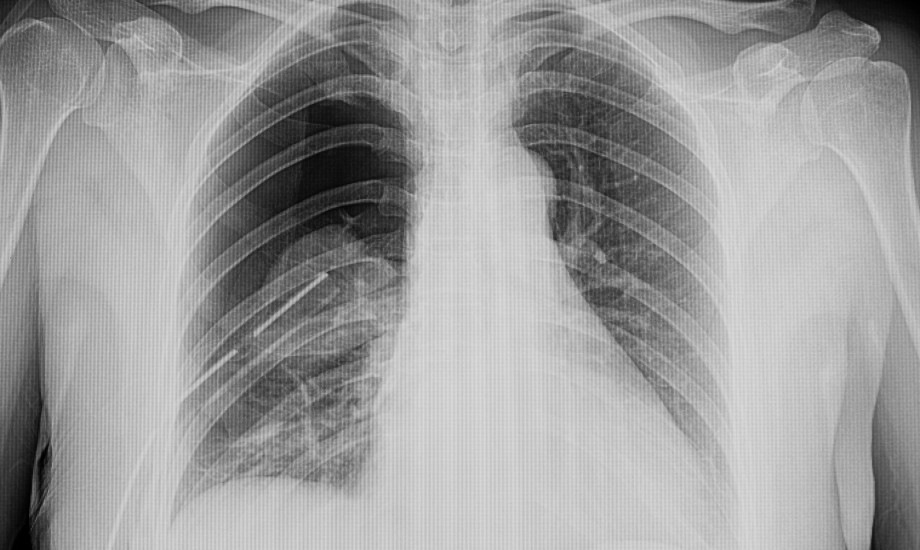

Eine 15-jährige, bislang gesunde Jugendliche klagt über seit zwei Wochen zunehmende linksseitige belastungsabhängige Brustschmerzen. Eine Infektion oder ein Trauma liegen nicht vor, auch familiäre Risikofaktoren bestehen nicht.